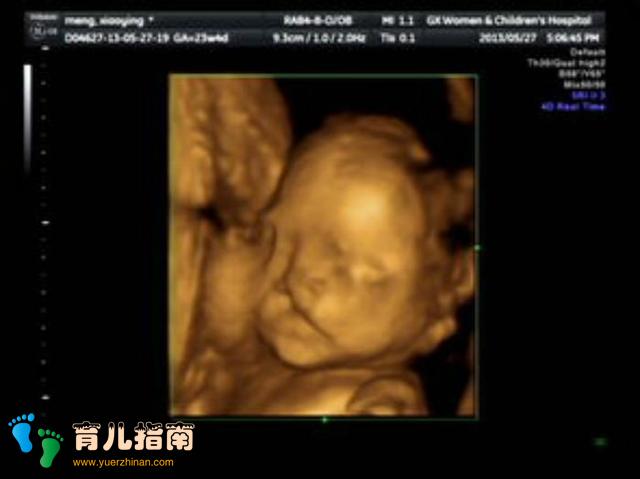

孕妇做B超看见胎儿一直在笑,以为宝宝很聪明,医生摇头叹了口气。医生看清了孩子的情况,他有很严重的唇裂问题,从嘴巴一直裂到耳朵,医生说按照现在的技术根本不可能修复好,所以就算孩子生下来对他也是一种折磨,还是不要让他遭罪了。小文听到这个结果很是崩溃,她觉得自己在孕期还是很注意的,怎么就会出现这个问题呢?